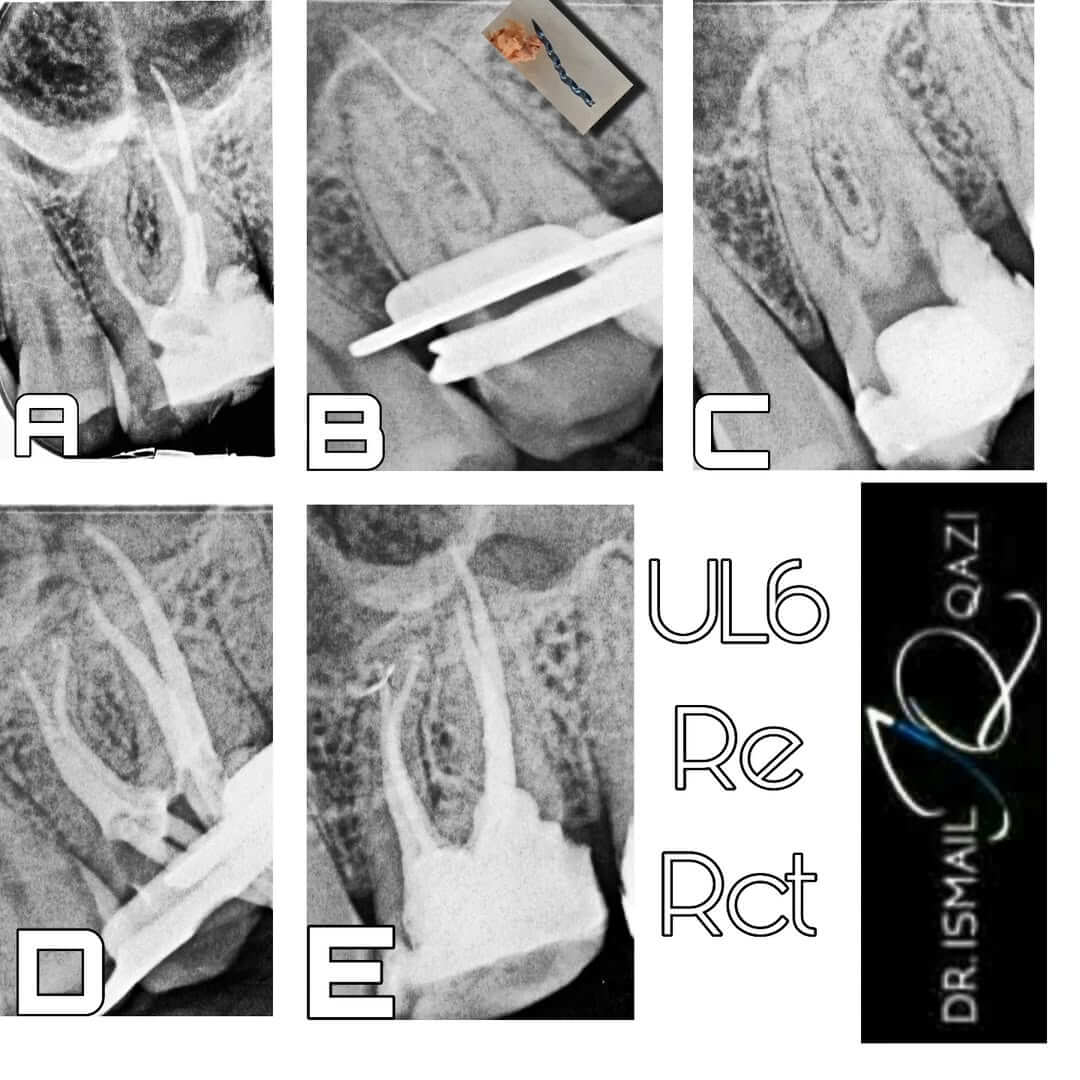

Complex Re-root Canal Treatments

Advanced techniques to retreat previous root canal treatments that haven't been successful.

Case Portfolio

View examples of successful treatments I've performed for patients with complex dental needs.